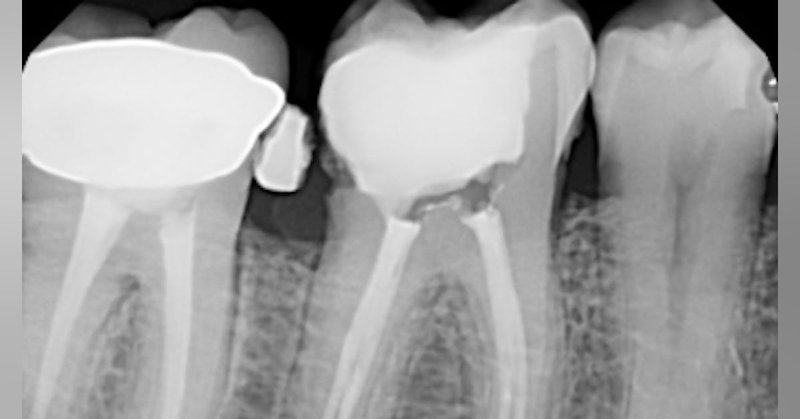

Transformation Tuesday: patient presented with pain on tooth 15. He had a RCT done on it 2 months earlier. The tooth is still tender to percussion and palpating. Diagnosis is a previously…